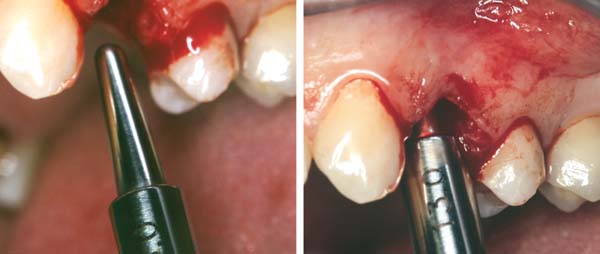

A 53-year-old female was referred for evaluation of a fracture of tooth No. 24. The tooth had been treated endodontically 5 years prior. The radiograph revealed a complete fracture of the tooth involving the crown (Figure 12). Tooth extraction and immediate placement of a an implant that was 10 mm in length and 3.75 in diameter was planned.

At the time of surgery, the tooth was extracted without harvesting any mucosal flap because the implant site was prepared by means of a pilot drill bur (Figure 13) and alternating osteotomes (Figure 14A and Figure 14B). The implant was positioned and showed primary stability. The implant was loaded 2 days after surgery. Then, splinted PFM crowns supported by custom gold abutments were delivered. At 6 months posttreatment, the radiograph revealed no bone resorption and the clinical result was optimal (Figure 15A and Figure 15B).

Figure 13 The drill bur was used to start the implant site preparation.

Figure 14A and Figure 14B Alternating osteotomes were used to prepare the implant site.